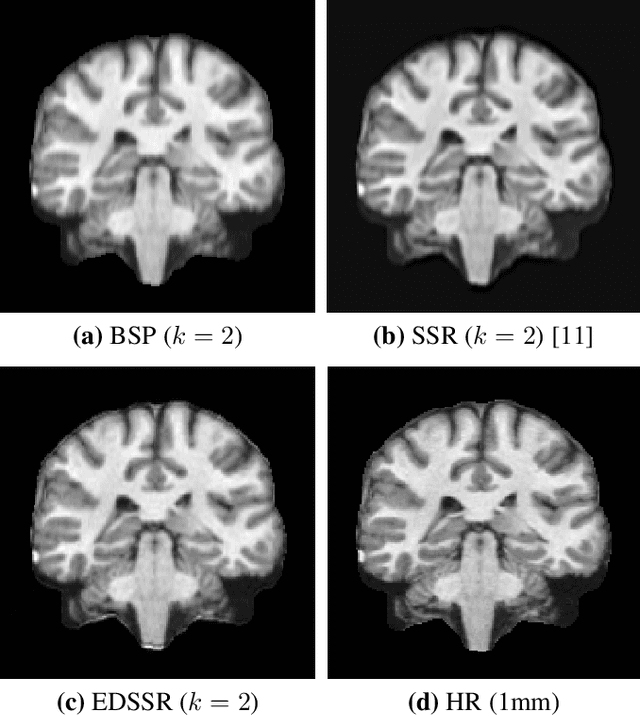

High resolution magnetic resonance~(MR) imaging~(MRI) is desirable in many clinical applications, however, there is a trade-off between resolution, speed of acquisition, and noise. It is common for MR images to have worse through-plane resolution~(slice thickness) than in-plane resolution. In these MRI images, high frequency information in the through-plane direction is not acquired, and cannot be resolved through interpolation. To address this issue, super-resolution methods have been developed to enhance spatial resolution. As an ill-posed problem, state-of-the-art super-resolution methods rely on the presence of external/training atlases to learn the transform from low resolution~(LR) images to high resolution~(HR) images. For several reasons, such HR atlas images are often not available for MRI sequences. This paper presents a self super-resolution~(SSR) algorithm, which does not use any external atlas images, yet can still resolve HR images only reliant on the acquired LR image. We use a blurred version of the input image to create training data for a state-of-the-art super-resolution deep network. The trained network is applied to the original input image to estimate the HR image. Our SSR result shows a significant improvement on through-plane resolution compared to competing SSR methods.